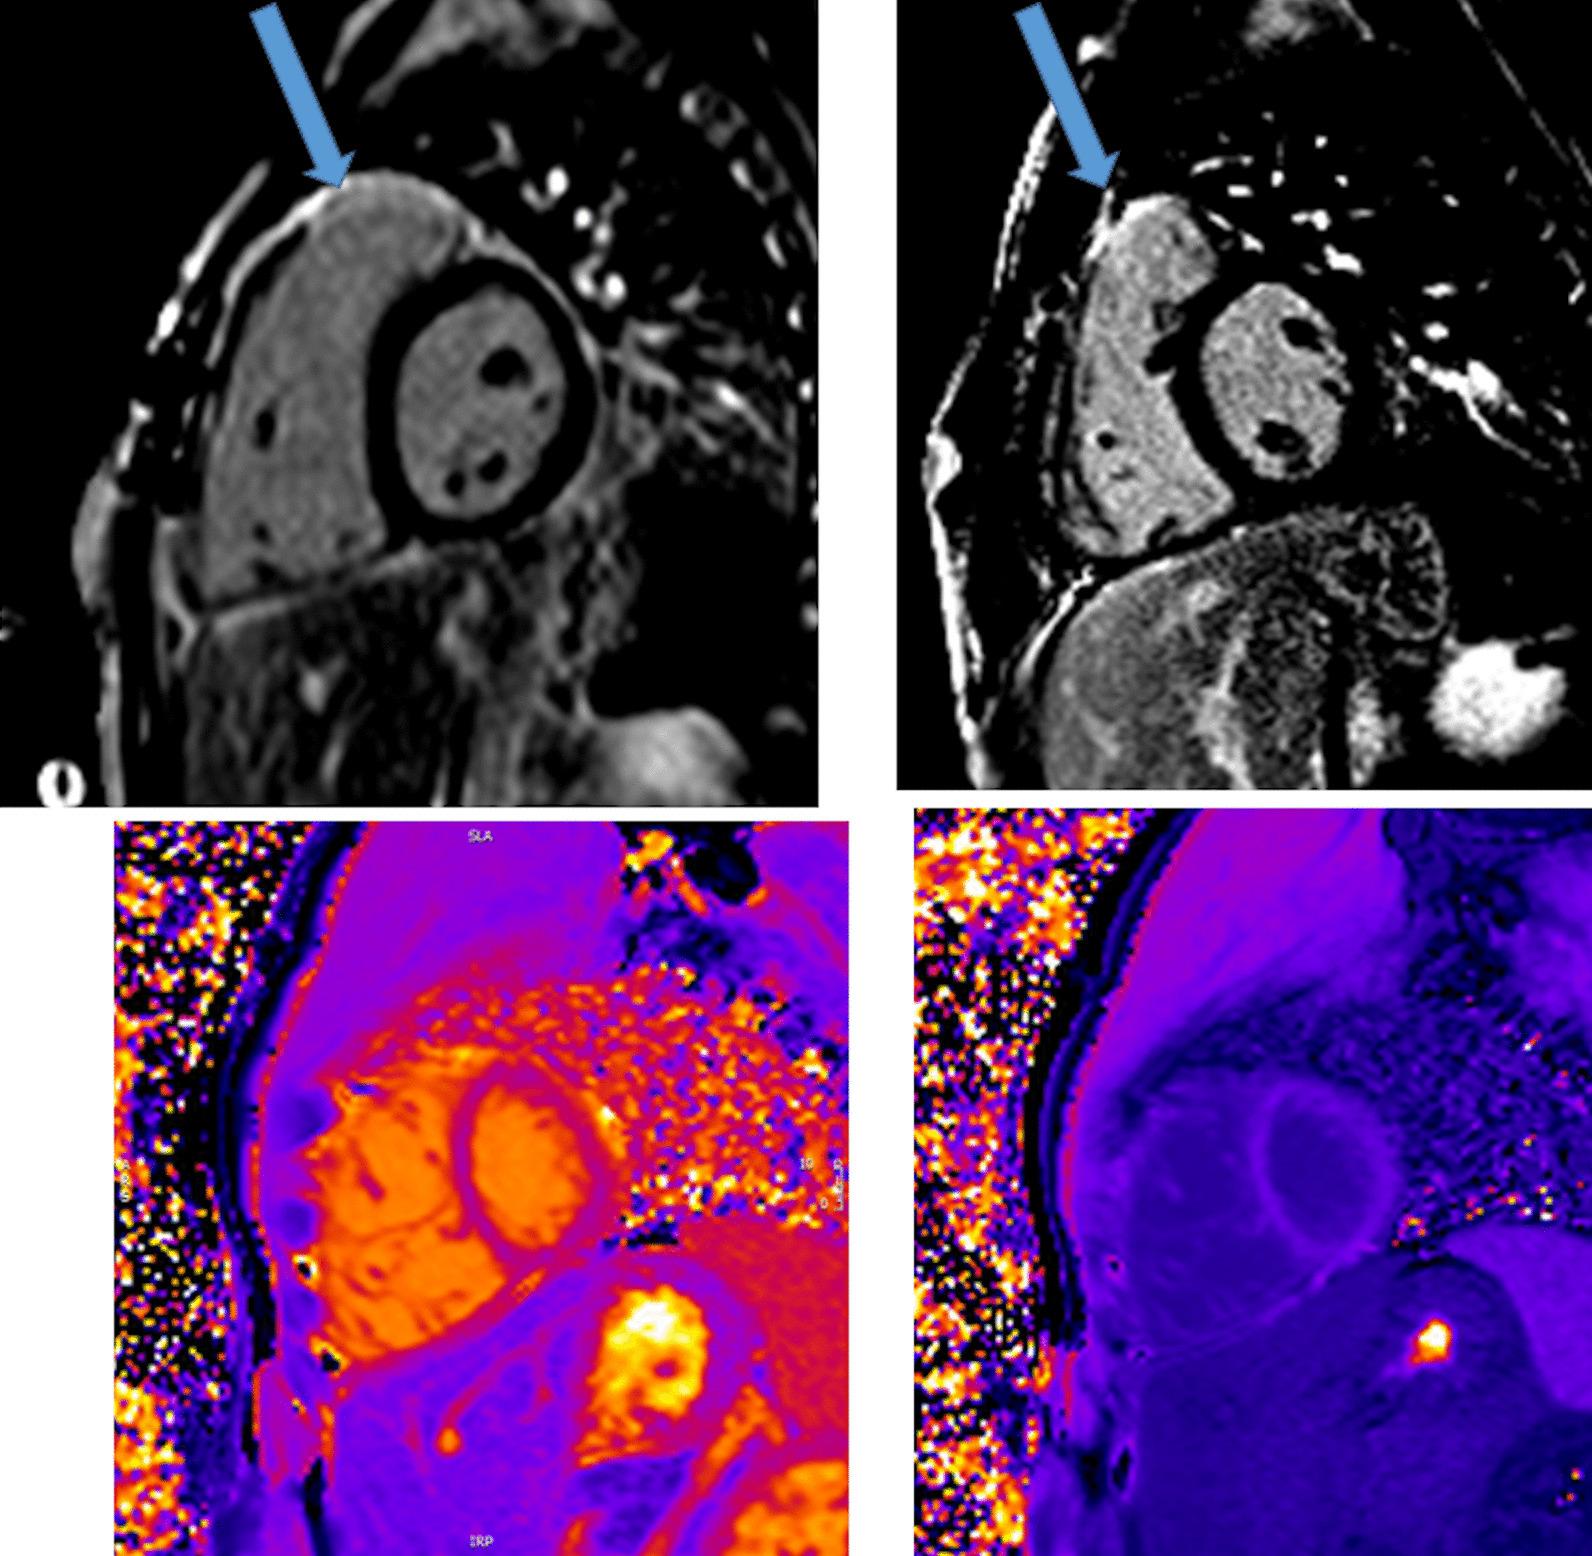

Cardiovascular magnetic resonance (CMR) has been utilized in the management and care of pediatric patients for nearly 40 years. It has evolved to become an invaluable tool in the assessment of the littlest of hearts for diagnosis, pre-interventional management and follow-up care. Although mentioned in a number of consensus and guidelines documents, an up-to-date, large, stand-alone guidance work for the use of CMR in pediatric congenital 36 and acquired 35 heart disease endorsed by numerous Societies involved in the care of these children is lacking. This guidelines document outlines the use of CMR in this patient population for a significant number of heart lesions in this age group and although admittedly, is not an exhaustive treatment, it does deal with an expansive list of many common clinical issues encountered in daily practice.

心血管磁共振(CMR)在儿科患者的管理和护理中已经应用了近 40 年。它已经发展成为评估最小的心脏的宝贵工具,用于诊断、介入前管理和随访。尽管在许多共识和指南文件中提到,但在儿科先天性心脏病和后天性心脏病领域,目前还缺乏一份由众多参与儿童护理的学会共同认可的、最新的、独立的、针对 CMR 使用的大型指南。本指南文件概述了 CMR 在该年龄段的许多心脏病变中的应用,尽管不能说是详尽的治疗方法,但它确实涉及了在日常实践中经常遇到的许多常见临床问题的广泛列表。